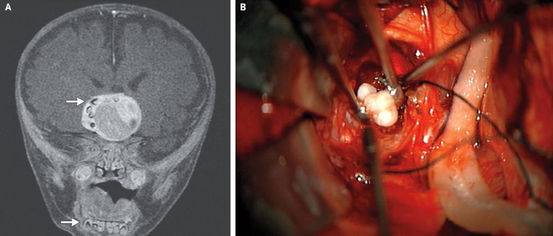

11、脑内长牙

美国一名4个月的患儿因一种少见的脑肿瘤而脑内长出牙齿。

手术中发现患儿脑内的肿瘤已经长出了数颗发育完整的牙齿。术中取活检证实该肿瘤为颅咽管瘤,一种大约高尔夫球大小但是不易扩散的肿瘤。

尽管一直有专家猜测这种肿瘤细胞和发育成牙齿的细胞是同类,但是在这个案例之前并没有这种肿瘤真的生成了牙齿的案例报道。

也就是说这是世界首例。

这个案例发表在2014年的扭英上。